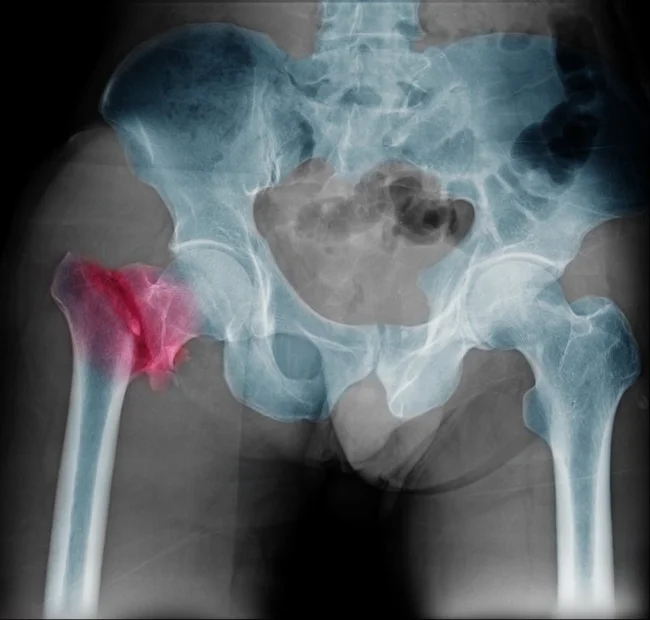

Нове дослідження показало, що чай може знижувати ризик переломів шийки стегна у жінок старшого віку, тоді як надмірне вживання кави, навпаки, може його збільшувати. Вчені з Університету Фліндерса в Аделаїді вивчили дані за 10 років, порівнявши звички пити чай і каву з показниками міцності кісток стегна ключовим фактором ризику переломів.

Вчені з'ясували, що до трьох чашок кави на день не шкодить кісткам, але надмірне споживання може бути небезпечним. У тих, хто пив понад п'ять чашок на день, було виявлено низьку мінеральну щільність кісткової тканини. Це підвищує ризик переломів стегна у майбутньому.

Згідно з офіційними даними, кожна третя жінка і кожен п'ятий чоловік старше 50 років страждає на остеопороз.

Захворювання розвивається повільно, протягом кількох років. Часто його діагностують, коли перелом відбувається через падіння чи удар.

Найчастіші переломи – зап'ястя, шийки стегна та хребців.